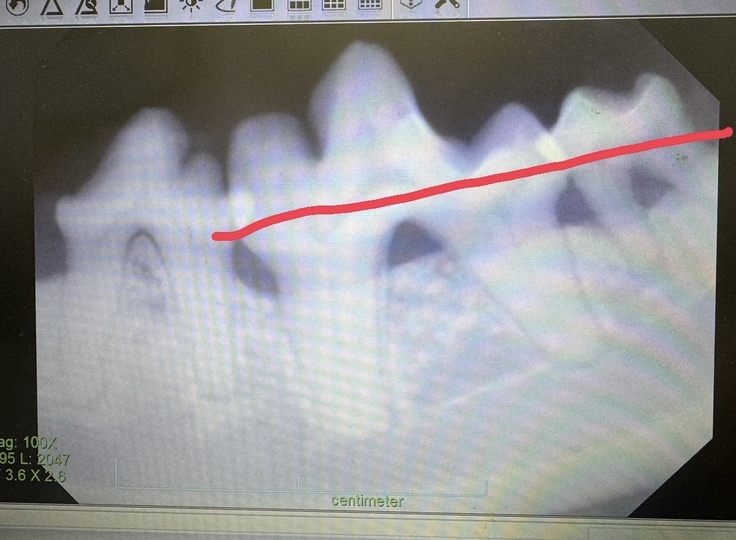

手術途中に先生から電話があり、全身麻酔をしてからレントゲンを撮ったところ重度の歯周病になっていて、歯槽骨が溶けてしまっていたそうです。

本当はまだ若いから残せる歯は残したいということでしたが、レントゲンからみると全ての歯が抜歯対象とのことでした。

この写真でいうと、本来赤い線まで歯茎がなければいけませんが、溶けてなくなっている状態でした。

《 レントゲン画像 》